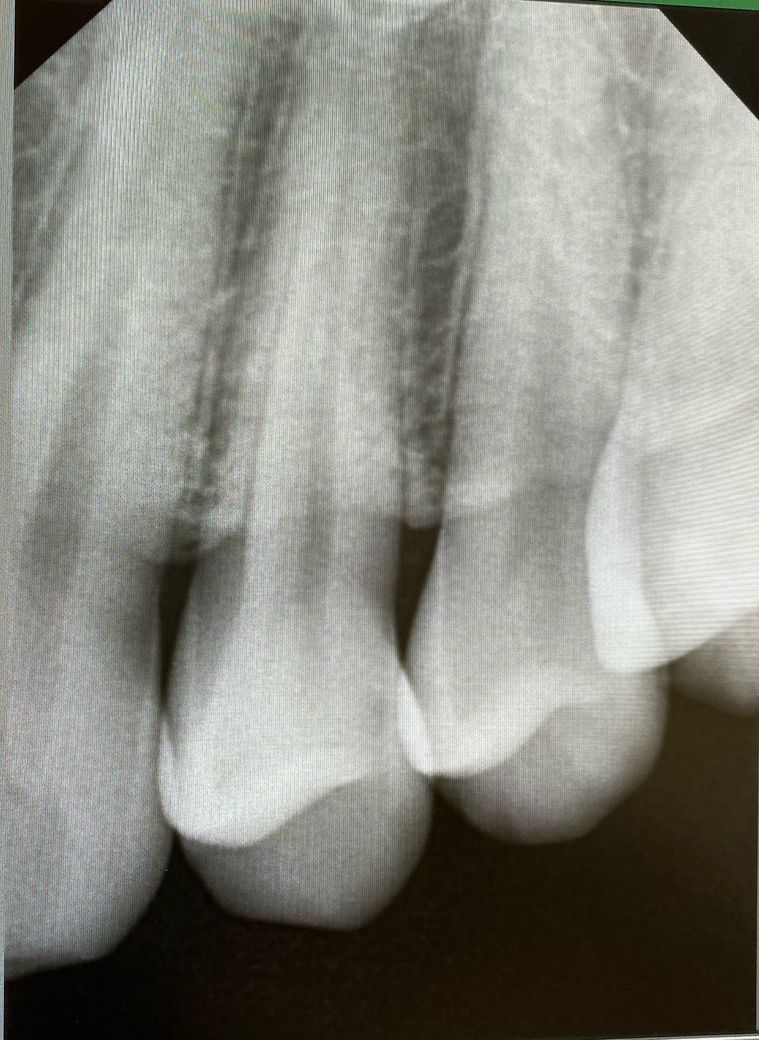

1번 치과는 왼쪽 위 4번째 안쪽면에 인접면 충치

인접면 충치 재료를 gi와 레진도 가능하다는데

육안상으로보면 치아 사이에 충치가 잇는거 같습니다. 관리를 잘하시면 진행이 안되겟지만 관리가 안되면 충치 진행이 빨라져서 신경치료를 해야될수도 잇으니 저라면 미리 치료를 하라고 권유할것같습니다 .

육안으로 봤을 경우에는 인접면에 충치가 있는 것으로 보이긴 합니다. 하지만 엑스레이 사진상으로 크게 보이지 않기 때문에 관리를 해서 사용할 수 있는 경우도 있습니다. 충치가 더 커지는 것을 방지하기 위해 예방적으로 치료를 하고자 한다면 치료가 필요할 수 있으며 그렇지 않다면 관리를 하면서 상태를 지켜볼 수 있습니다.

치료여부는 평상시 관리상태나 구강상태에 따라 갈릴 수 있으며 지아이는 거의 쓰지 않습니다.